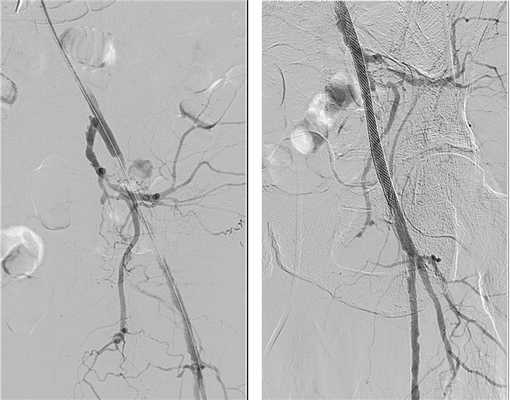

Чрескожная ангиопластика начинается доступом к сосуду по пульсации, а если она отсутствует, то пункция проводится по анатомическим ориентирам, но в нашей клинике для доступа используется ультразвуковое сканирование в B-режиме. После попадания иглой в сосуд проводится тонкий проводник, по которому устанавливается специальная трубочка - интрадьюссер с клапаном на конце и возможностью промывания. Затем выполняется введение контраста - ангиография для уточнения тактики операции. Проводник проводится до места сужения, преодолевает это сужение и проводится дальше. После прохождения всех сужений по проводнику проводится баллон, который раздувается и моделирует просвет сосуда (ангиопластика). После этого проводится контрольная ангиография и если выявляется расслоение стенки артерии, то в это место необходимо установить стент, подходящий по диаметру.

После проведения ангиопластики и стентирования обязательно проводится контрольная ангиография для оценки результата.